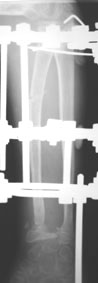

Лучевая косорукость

11-летний любитель лазить по деревьям 7 месяцев назад получил открытый дистальный остеоэпифизеолиз левого луча. ПХО была сделана с трудом; о репозиции, со слов, и не помышляли. Неделю назад удалось открыто адаптировать костные фрагменты, фиксировать аппаратом. Сразу сделали кортикотомию в/3 луча. Начали его удлинение. Вопрос: учитывая отсутствие дистальной зоны роста стоит ли "переудлинить" луч? Если да, то на какую величину?